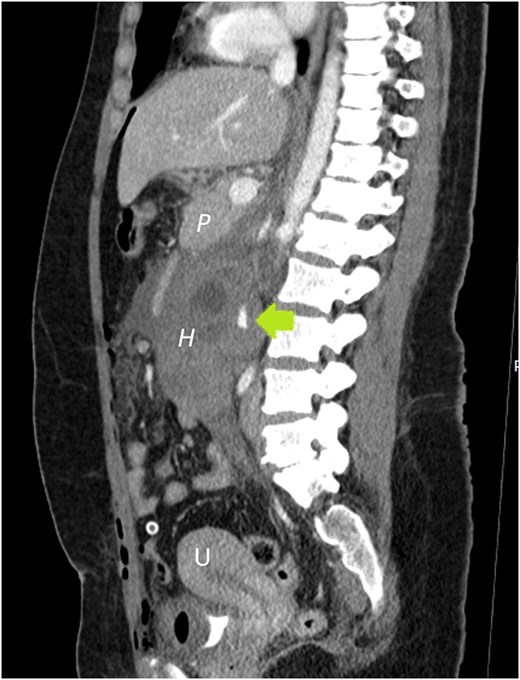

She underwent abdominal sonography followed by contrast-enhanced computed tomography (CECT). Both demonstrated a right-sided retroperitoneal hematoma adjacent to the inferior vena cava and right kidney. A 5 cm ring-shaped structure resembling an empty gestational sac was detected inside the hematoma (Fig. 1). CT showed contrast extravasation representing active bleeding (Figs 2 and 3). Interdisciplinary team discussion, including obstetrician-gynecologists, abdominal surgeons, anesthesiologists, and radiologists, led to the decision for emergency relaparotomy.

A growing slit-like focus of active extravasation was detected on arterial (a) and venous (b) phase scans, obtained 30 and 70 seconds after contrast injection, respectively.

Sagittal plane CECT shows the hematoma (H) displacing the pancreas ventrally, proving its retroperitoneal location. Active bleeding is seen adjacent to the gestational sac (arrow). A normal appearing, nonpregnant uterus is also visible.